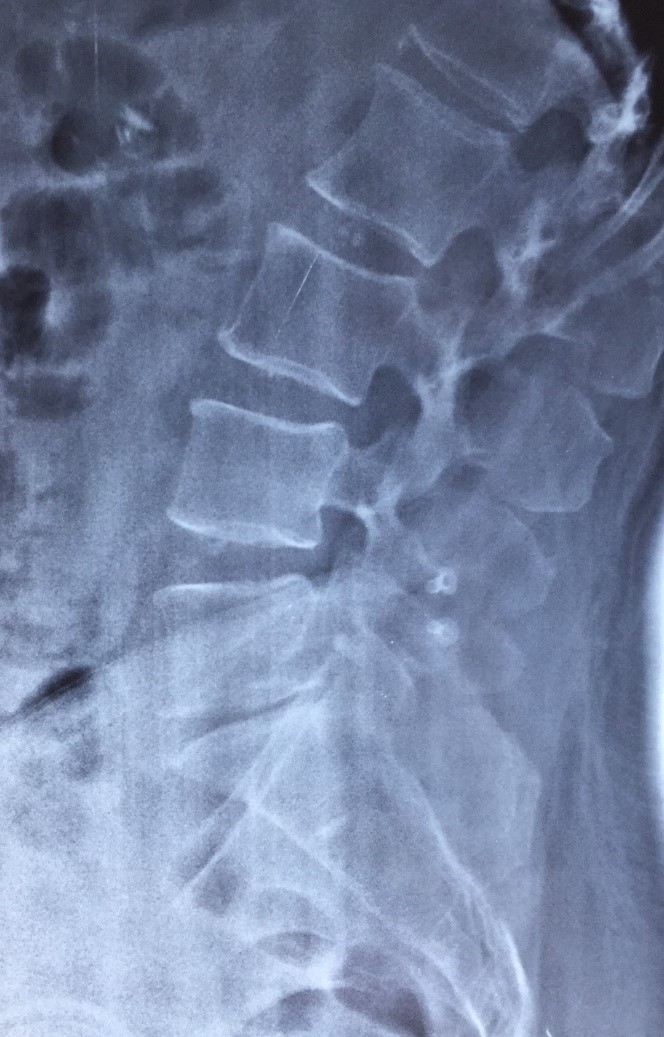

Radiografia da coluna lombar antes da cirurgia evidenciando importante desgaste do último disco vertebral L5/S1.